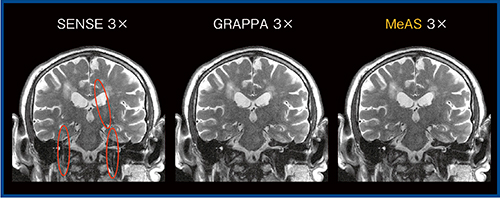

また,MeASの特長として,マップスキャンを行わないためマップ画像との位置ズレによるアーチファクトが発生しない,イメージベースで展開するためSNRの低下が少ない,高速化時の展開アーチファクトが非常に少ない,小FOV時の展開エラーが発生しづらい,体動などの動きも補正される,などが挙げられる。各種parallel imaging法の画像を比較すると,MeASではSENSEに見られるエッジアーチファクト(展開エラー)もなく,明瞭な画像が得られている(図2)。

図2 各種parallel imagingの画像比較(W.I.P.)